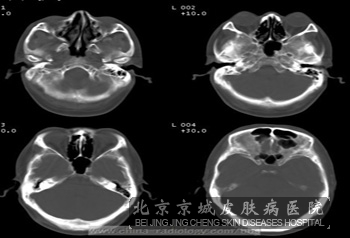

结节硬化症神经的损害结节硬化症神经的损害有哪些呢?结节硬化症患者一般会有很多方面的损害,一般就是皮肤症状以及一些神经系统的损害,其中皮肤就是皮脂腺瘤损害以及一些色素脱失斑。那么结节硬化症神经的损害有哪些呢?

结节硬化症神经的损害为智力低下以及癫痫症状,其中癫痫患者一般会早很早就会出现,而且开始为婴儿痉挛症,之后会出现全身性发作或部分性发作;但是有些患者仅有癫痫发作而无其他临床表现,但是有些病人有不同程度的智力减退常在2~3岁即出现,甚至更早有智能障碍者几乎均有癫痫发作。